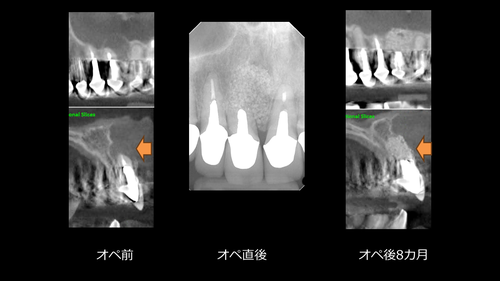

スライド5.PNG前歯部の大きな歯根嚢胞の摘出も非常に経過良好です。